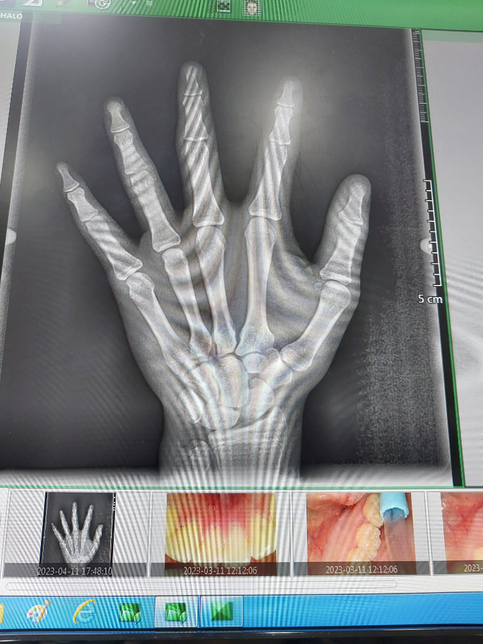

- 기타 고민상담고민상담Q. 중3 남자 키 관련 질문 입니다. 진지하게 답변해주시면 감사하겠습니다.현재 중3 남자 만나이:15세 입니다 밑에 있는 사진은 2023년 4월 11일에 찍은 오른쪽 손 x-ray 사진 입니다. 참고로. 현재 겨드랑이털 나고 있습니다,성기에 털이 나고 있고요 그리고 턱수염도 현재 나고 있습니다 그리고 유전적키는 얼마나 클수 있을까요? 부모님키 아버지:170cm 어머니:160cm 입니다 그리고 저의 현재키는 아침에 일어났을때에는 딱 170cm가 됩니다 그리고 저녁에 쟀을때는 168.8cm 입니다 제가 성장이 완료 됬을때에는 키가 얼마나 더 클수있을까요?